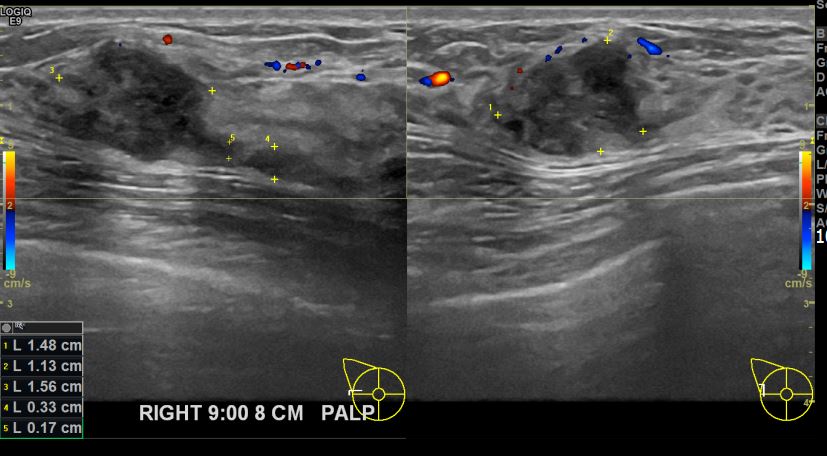

상기환자 우측유방멍울 만져져 내원하신 30대 여성분으로 유방암 의심혹 조직검사 시행 후 유방암 진단되었습니다.